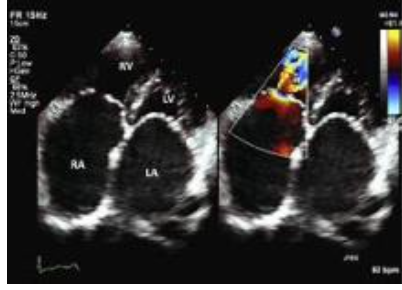

Tricuspid Regurgitation

definition

A

the result of an incompetent TV that permits backward systolic from the RV, through the TV (while it is closed), into the RA

_Tricuspid Regurgitation_ 2D echo findings

\*anatomic basis/defect that prevent coaptation: * **RA enlargement** with dilated annulus * thickened TV leaflets, particularly if there is a history of RHD * **TVP,** best detected from the PLAX RVIT, 4C, or Sub \***diastolic flutter of the TV leaflets** secondary to trauma or endocarditis \*_RV volume overload pattern_: **RV dilatation with paradoxical septal motion** - note: chronic, severe TR usually leads to RA/RV dilatation; whereas, normal chamber volume are **_unusua_**l with chronic, severe TR \*dilated IVC (normal: 1.2 - 2.1 cm) \*dilated HV (normal: 0.5 - 1.1 cm) * trauma * endocarditis